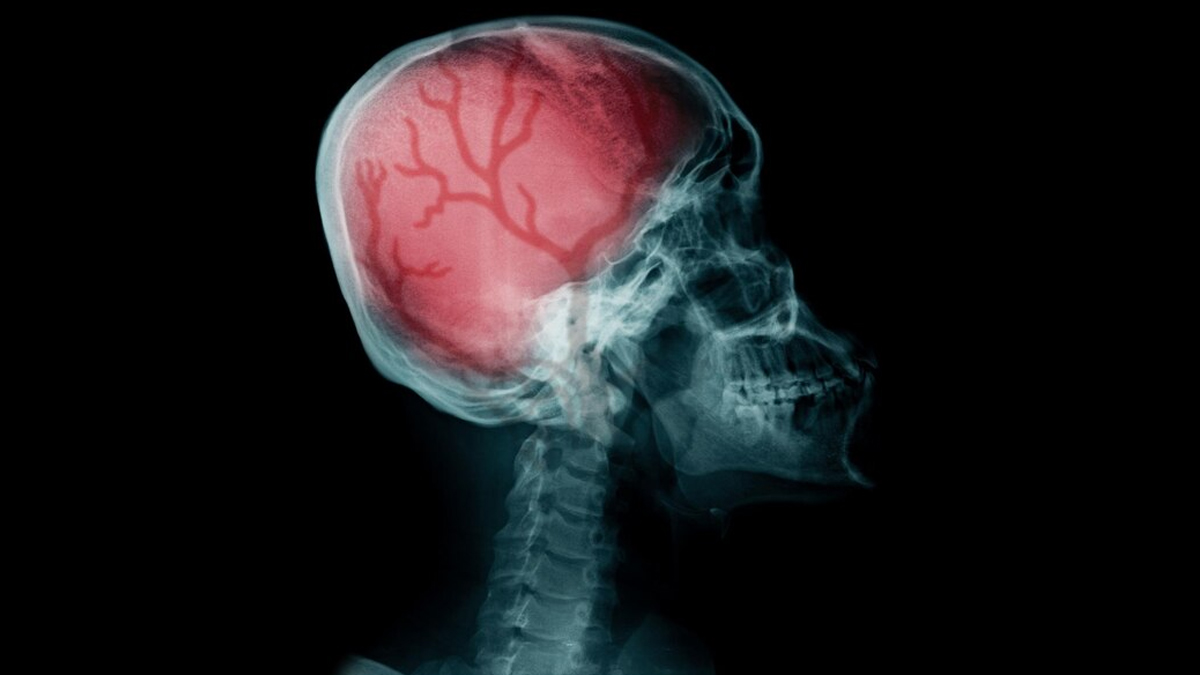

We all know how dangerous a head injury can be. Patients of traumatic brain injury can end up in life-long comas, or suffer serious cognitive decline. Recovering from a serious head injury can be quite a challenge, especially if the treatment modalities consited of complex surgeries. To increase the chances of recovery, personal measures are just as important as medical support after agetting a brain injury treated.

Recovering from a traumatic brain injury (TBI) can be a challenging journey, but there are several tips and strategies that can help minimise long-lasting effects and promote a smoother recovery. Dr Tyagi recommended, “You have to stimulate and strengthen your mind as much as possible so that you can get back to your normalroutine.”